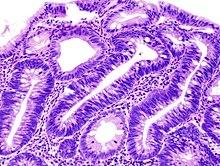

Ein Adenom ist eine gutartige Wucherung, die sich aus der obersten Zellschicht von Drüsengewebe, wie zum Beispiel der Schilddrüse oder der Schleimhaut des Magen-Darm-Traktes, entwickelt. Diese Wucherungen entstehen durch eine unkontrollierte Vermehrung von Zellen in den Drüsen oder Schleimhäuten.

Ein Adenom ist eine gutartige Wucherung, die sich aus der obersten Zellschicht von Drüsengewebe (z.B. der Schilddrüse) oder der Schleimhaut des Magen-Darm-Traktes entwickelt. Es handelt sich dabei um eine abnormale Vermehrung von Zellen, die zu einer Neubildung von Gewebe führt.

Ein Adenom ist eine gutartige Wucherung, die sich aus der obersten Zellschicht von Drüsengewebe oder der Schleimhaut des Magen-Darm-Traktes entwickelt. Es handelt sich dabei um eine abnormale Vermehrung von Zellen, die zu einer Gewebevergrößerung führt.

Adenome sind gutartige Wucherungen, die sich aus der obersten Zellschicht von Drüsengewebe oder der Schleimhaut des Magen-Darm-Traktes entwickeln. Sie entstehen, wenn bestimmte Zellen anfangen, sich unkontrolliert zu vermehren und eine abnormale Größe erreichen. Die genaue Ursache für die Entstehung von Adenomen ist noch nicht vollständig geklärt, aber es wird angenommen, dass genetische Veränderungen und Umweltfaktoren eine Rolle spielen können.

Ein Adenom ist eine gutartige Wucherung, die sich aus der obersten Zellschicht von Drüsengewebe oder der Schleimhaut des Magen-Darm-Traktes entwickelt. Es handelt sich dabei um abnormales Zellwachstum, das zu einer Verdickung oder Vergrößerung des Gewebes führt. Adenome können in verschiedenen Organen auftreten, wie zum Beispiel in der Schilddrüse oder im Darm.